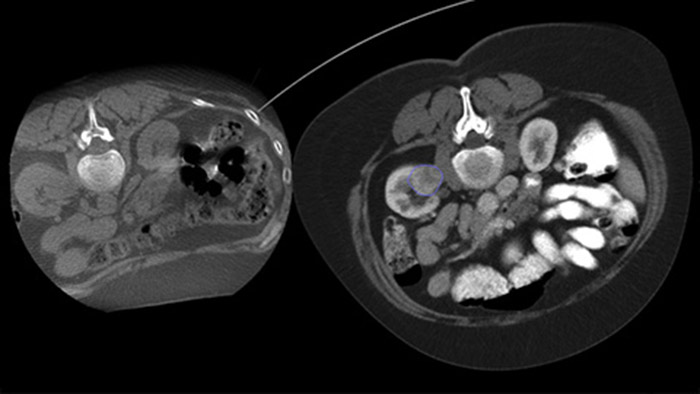

La ablación percutánea (radiofrecuencia, microondas y crioablación) es un tratamiento mínimamente invasivo de eficacia comprobada de tumores renales, hepáticos, pulmonares y óseos. Es fundamental definir los límites del tumor y decidir un número óptimo de agujas y la trayectoria de la aguja correspondiente para poder realizar un tratamiento tumoral completo y no causar daños en el tejido circundante. Navegar con precisión en dosis bajas hacia la lesión de interés sin necesidad de cambiar la posición de la aguja aumenta la oportunidad de éxito y reduce el riesgo de complicaciones en las biopsias o ablaciones. La confirmación del criterio de valoración del tratamiento de ablación se puede lograr con imágenes 3D mientras el paciente aún se encuentra en la mesa.

Con CBCT, adquiera una CBCT posterior a la ablación para demostrar el alcance de la cobertura del tumor y confirmar la integridad de su tratamiento.